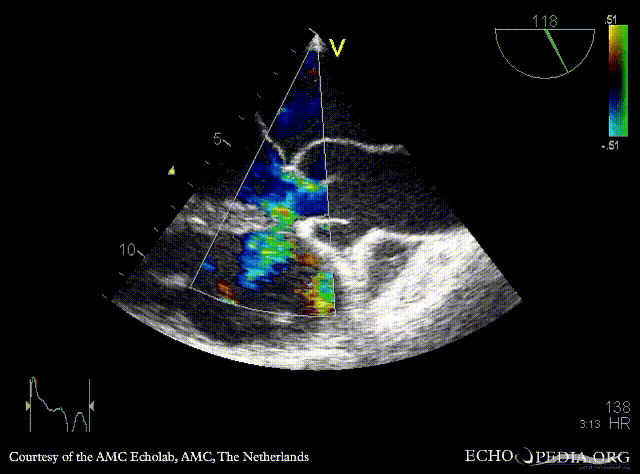

| TEE: muscular VSD

TEE: muscular VSD